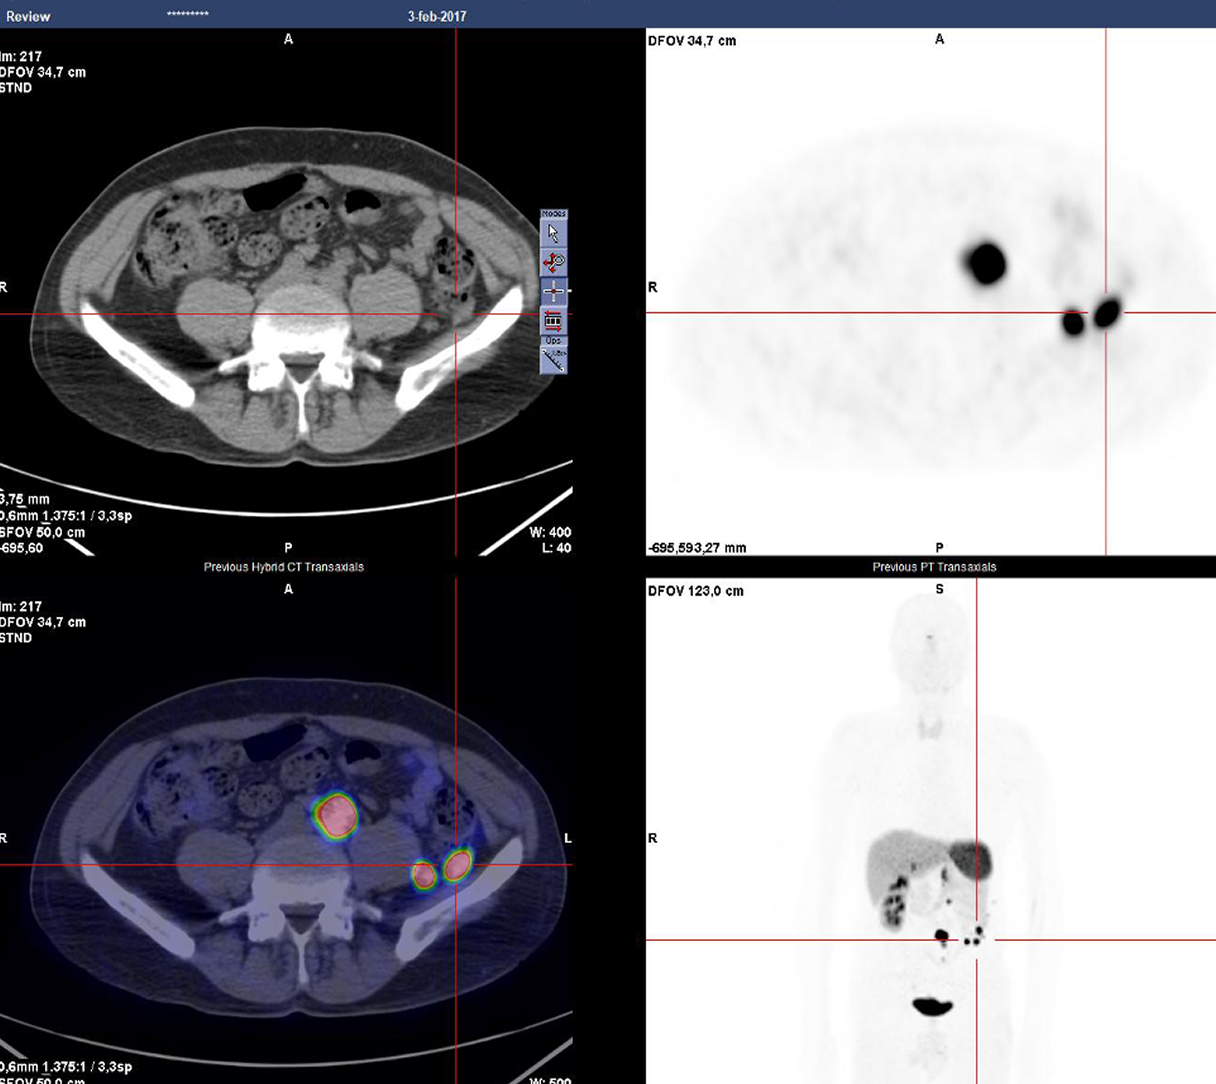

Casi clinici

Scopri come le tecnologie di imaging più innovative di GE HealthCare hanno giocato un ruolo chiave nella diagnosi di condizioni cardiache complesse.